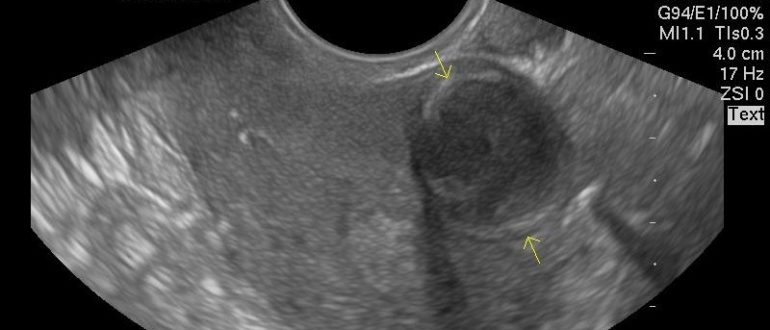

Миома или беременность

Как протекает беременность при миоме? Миома матки представляет собой одну из самых распространенных разновидностей опухолей, диагностирующихся в женской репродуктивной системе. Она диагностируется как у молодых женщин, так и…